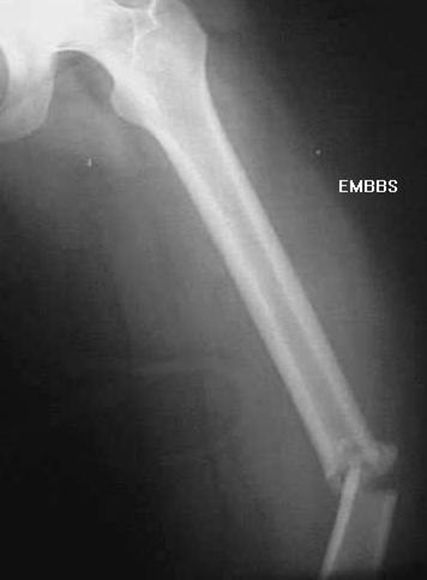

股骨干骨折